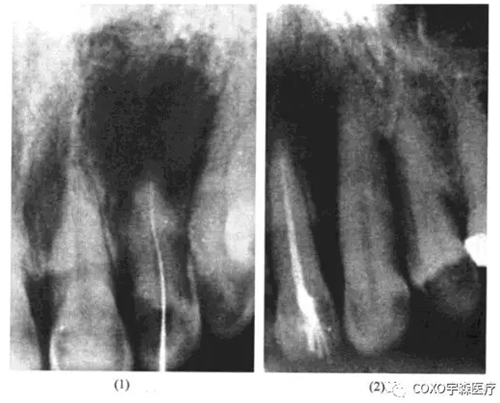

女性,54歲,左上唇炎癥腫脹一周在某中心醫(yī)院口腔科靜脈滴注抗生素未見好轉(zhuǎn)而來我科求治。檢查:[2唇側(cè)牙齦腫脹,有波動(dòng)感,[2無齲,無牙體缺損,牙髓活力測試反應(yīng)明顯,X線片示:[2根尖區(qū)有1cm×1.5cm之透射陰影,邊緣整齊。當(dāng)日處理:[2唇側(cè)切開引流待急性炎癥消退后,在局麻下行活髓摘除術(shù),牙髓完整,3日后完成根管充填,并行囊腫摘除術(shù)。術(shù)中見[2唇側(cè)骨板有極小的穿破,按常規(guī)刮除炎性肉芽組織,肉芽多在[2之腭側(cè),送病理切片;手術(shù)診斷為2根尖周囊腫,病理診斷亦為[2根尖周囊腫;3個(gè)月后復(fù)查,2無癥狀,X線片示:原根尖周病變已痊愈(圖13-4)

分析與評述

由于[2為活髓牙,根尖周囊腫的診斷不能成立。由于X線片示囊腫位于[2之根尖而非[23之間,術(shù)中亦證實(shí)囊腫在[2之根尖偏腭側(cè),故球上頜囊腫之診斷亦可排除,最后診斷應(yīng)為切牙管囊腫。